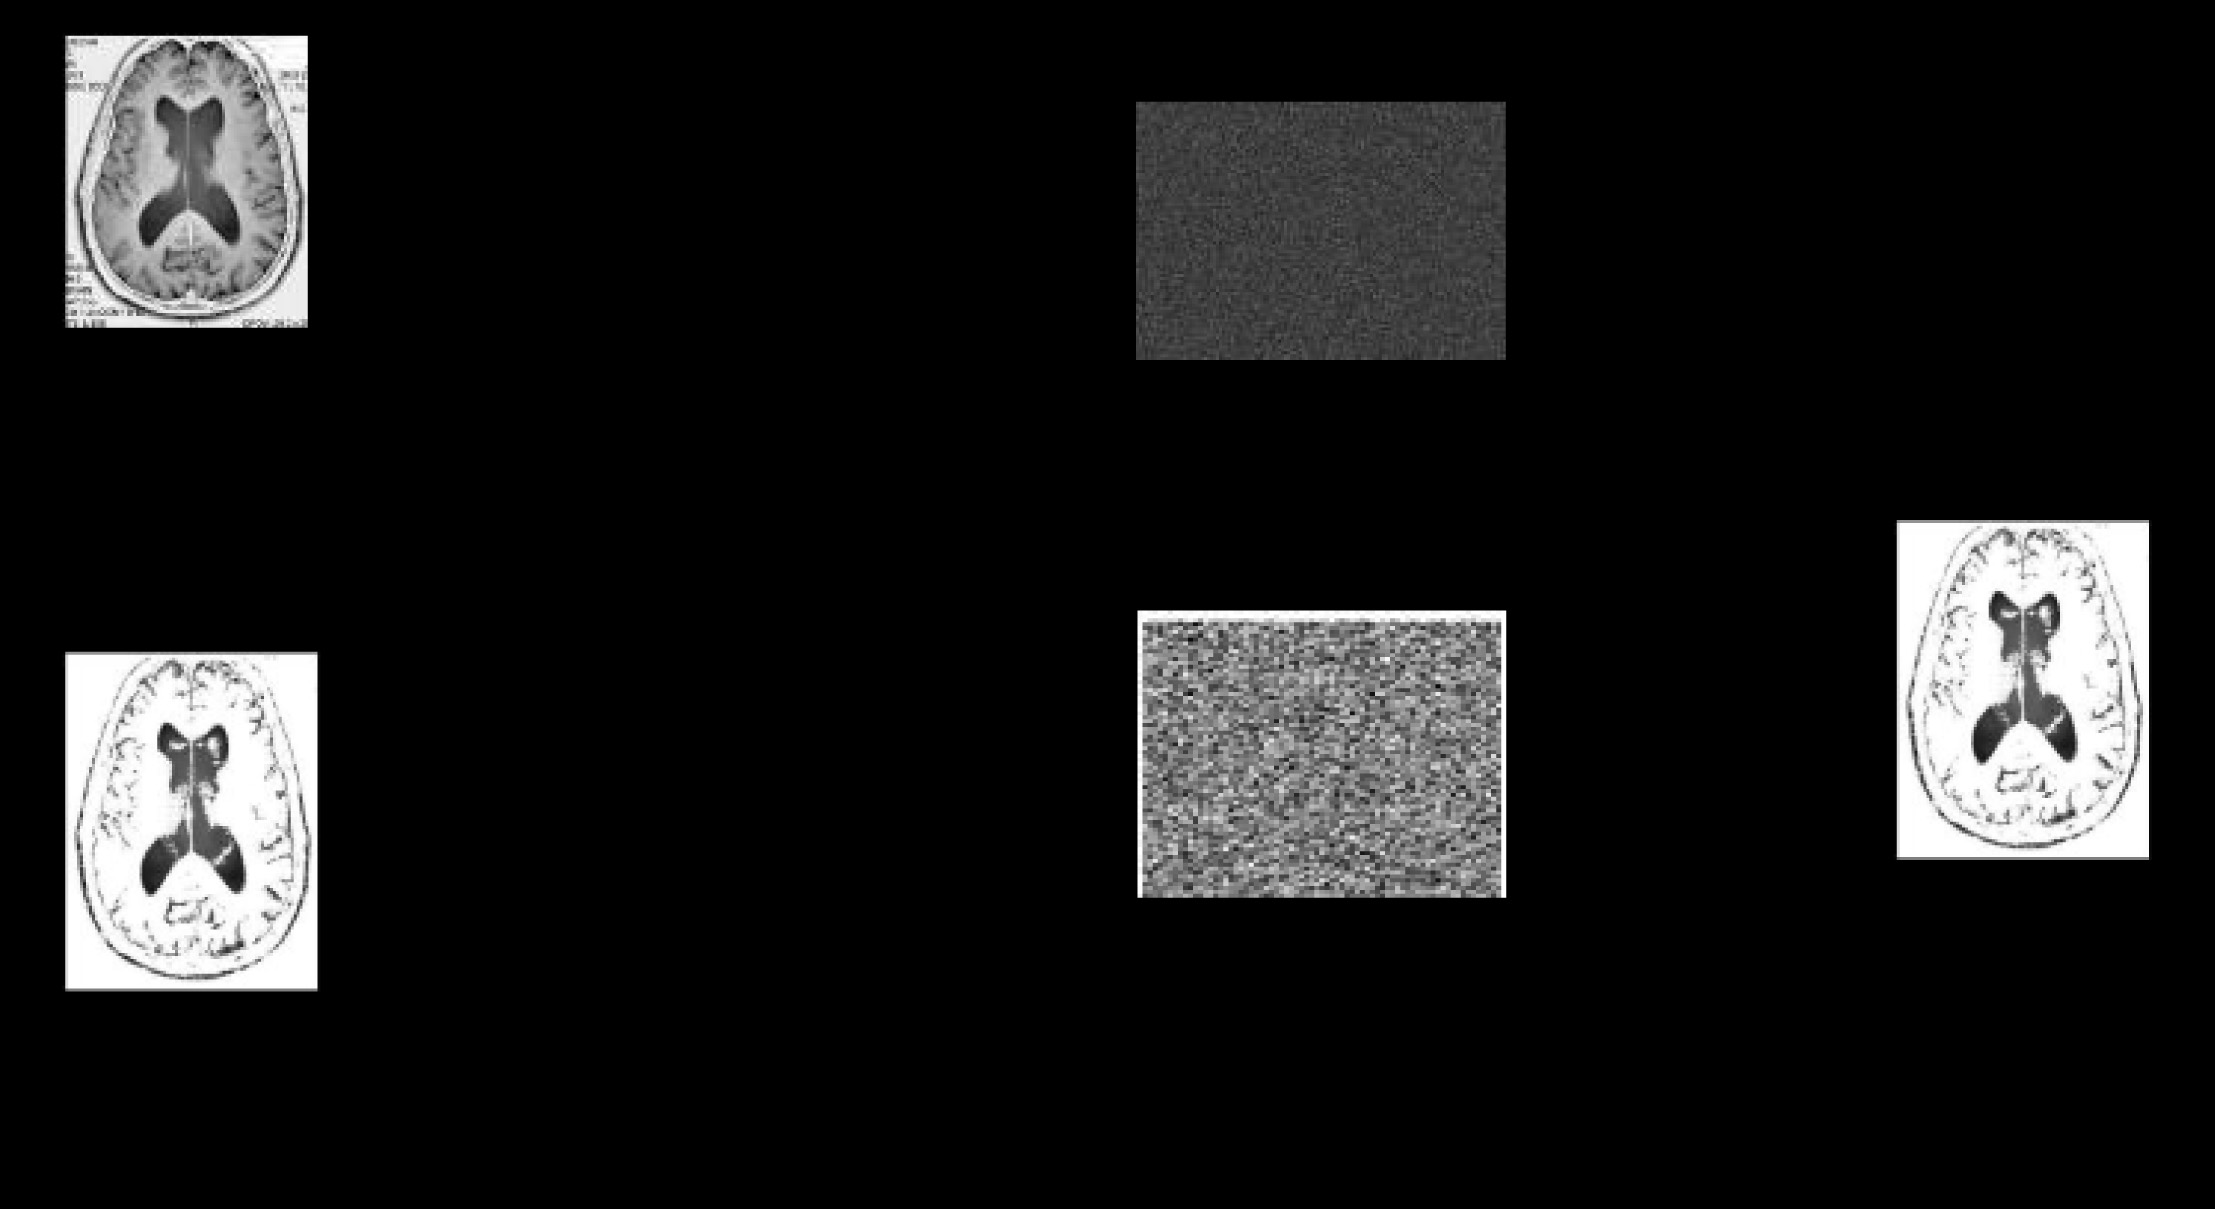

为了证明我们所提出概念的优势,本节将展示一个示例。因此,使用 MATLAB进行了仿真实验。在本研究中,我们使用一幅 256 × 256的医学图像 MRI。客户端从原始图像(a)中选择感兴趣区域,得到图像(b)。接着,将选定的部分分割为四个部分,如图(c)所示。实现结果如图8所示。

随后,我们在将每个子区域发送到CloudServ之前,使用EHES对其进行加密。CloudServ是一个多智能体系统,其中每个子区域由一个独立的智能体进行处理。